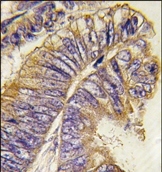

- Main image

- Experimental details

- Formalin-fixed and paraffin-embedded human colon carcinoma tissue reacted with PHLPP2 antibody (N-term), which was peroxidase-conjugated to the secondary antibody, followed by DAB staining.